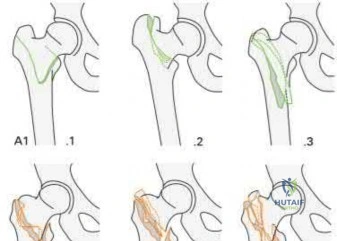

Question 4:

The Fraser classification describes floating knee injuries. Type I: True diaphyseal fractures of both the femur and tibia. Type IIA: Diaphyseal tibia with an intra-articular fracture of the femur. Type IIB: Diaphyseal femur with an intra-articular fracture of the tibia. Type IIC: Intra-articular fractures involving both the femur and tibia. The scenario describes a Type IIB floating knee.